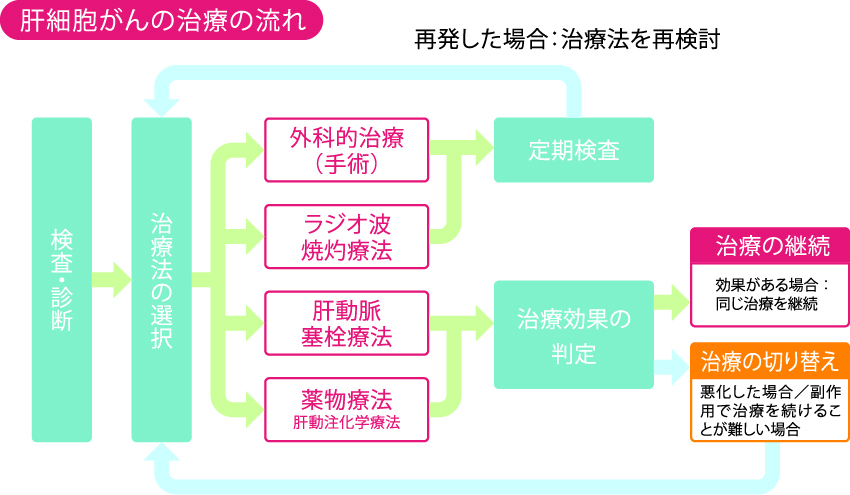

91c1V9loNrL.jpg, 肝細胞がん治療について|PLUS CHUGAI 中外製薬医療関係者向け,

肝細胞がん治療について|PLUS CHUGAI 中外製薬医療関係者向け, 京都大学肝胆膵・移植外科/小児外科 | 留学中の牧野 健太先生,

乳頭状尿路上皮癌 | MyPathologyReport, 中外肝細胞癌領域情報サイト Hepatocellar cartinoma|PLUS,

静岡製機 中古 穀物用循環型乾燥機 – 農キング, 肝細胞がん治療について|PLUS CHUGAI 中外製薬医療関係者向け,

肝細胞がん治療について|PLUS CHUGAI 中外製薬医療関係者向け, 002-504-14_M01_11.png,